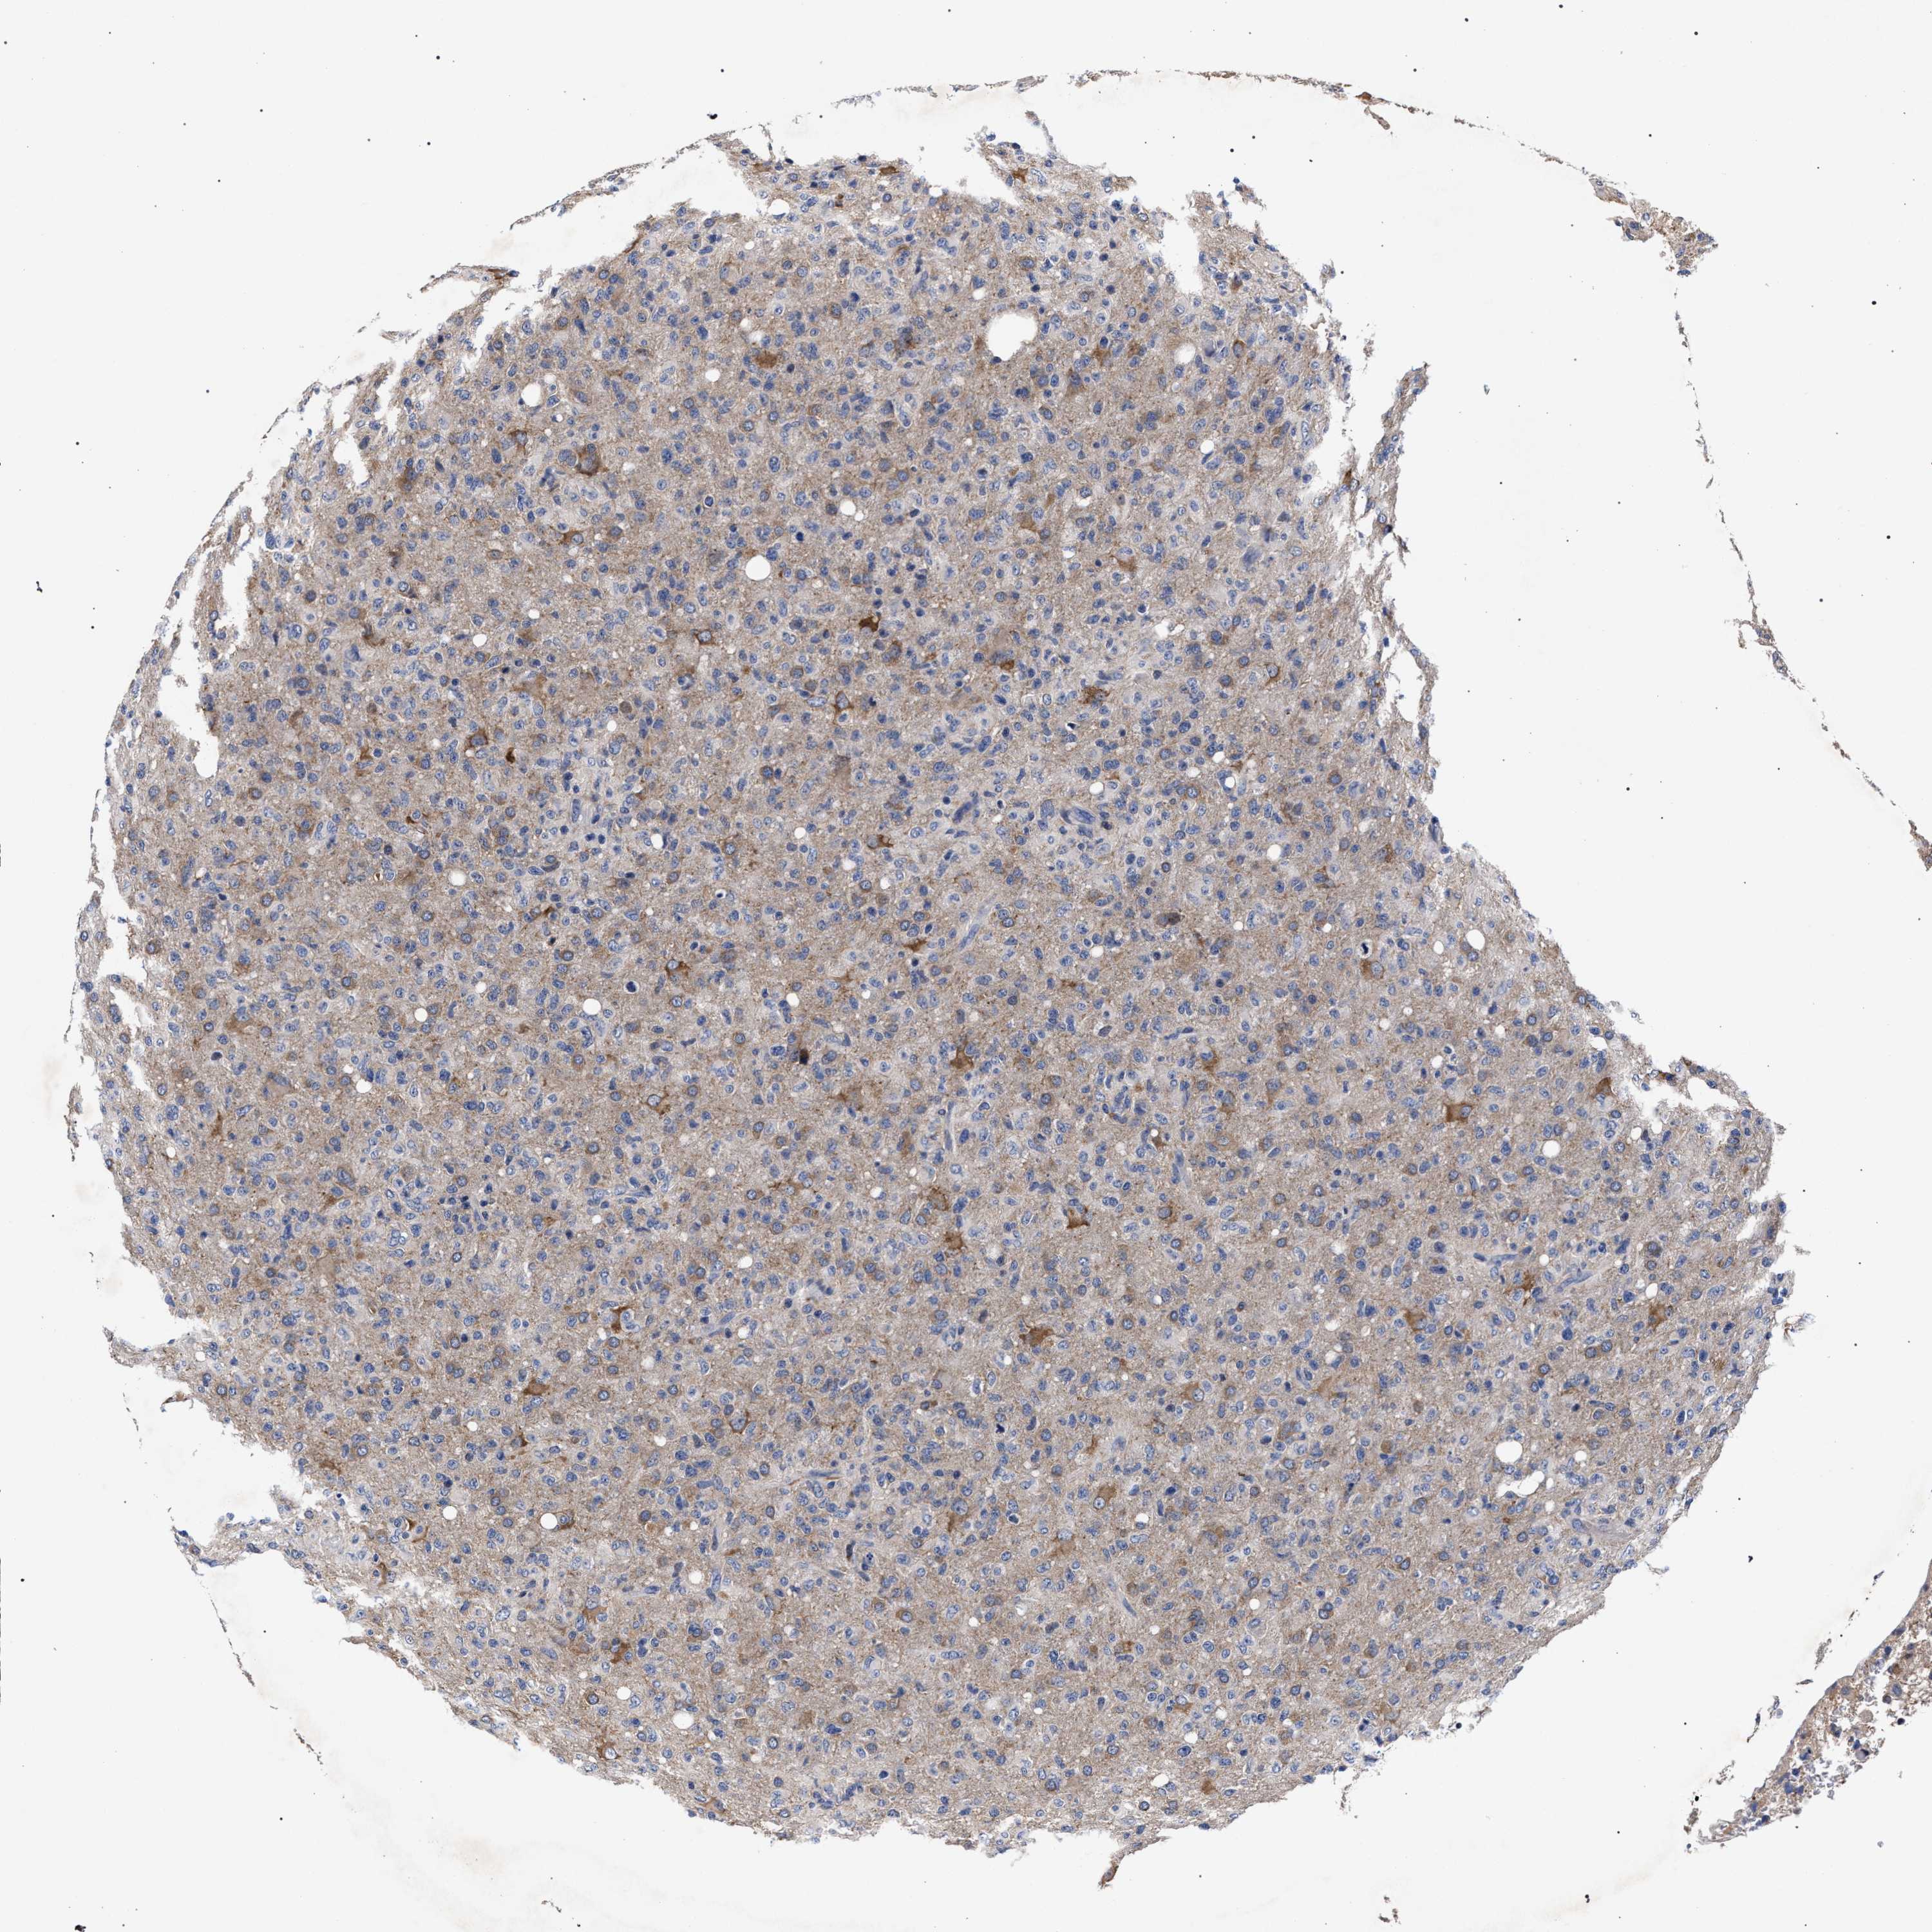

GLIOMA - Protein expressioni

A mouse-over function shows sample information and annotation data. Click on an image to view it in a full screen mode. Samples can be filtered based on level of antibody staining by selecting one or several of the following categories: high, medium, low and not detected. The assay and annotation is described here.

Note that samples used for immunohistochemistry by the Human Protein Atlas do not correspond to samples in the TCGA dataset.

Antibody stainingi

Antibody staining in the annotated cell types in the current human tissue is reported as not detected, low, medium, or high, based on conventional immunohistochemistry profiling in selected tissues. This score is based on the combination of the staining intensity and fraction of stained cells.

Each image is clickable and will lead to virtual microscopy that enables deeper exploration of all samples and also displays staining intensity scores, fraction scores and subcellular localization as well as patient and tissue information for each sample.

Antibody HPA021261

Antibody HPA021325

Staining

High

Medium

Low

Not detected

Intensity

Strong

Moderate

Weak

Negative

Quantity

>75%

75%-25%

<25%

None

Location

Nuclear

Cytoplasmic/membranous

Cytoplasmic/membranous,nuclear

Glioma, malignant, High grade

Glioma, malignant, Low grade